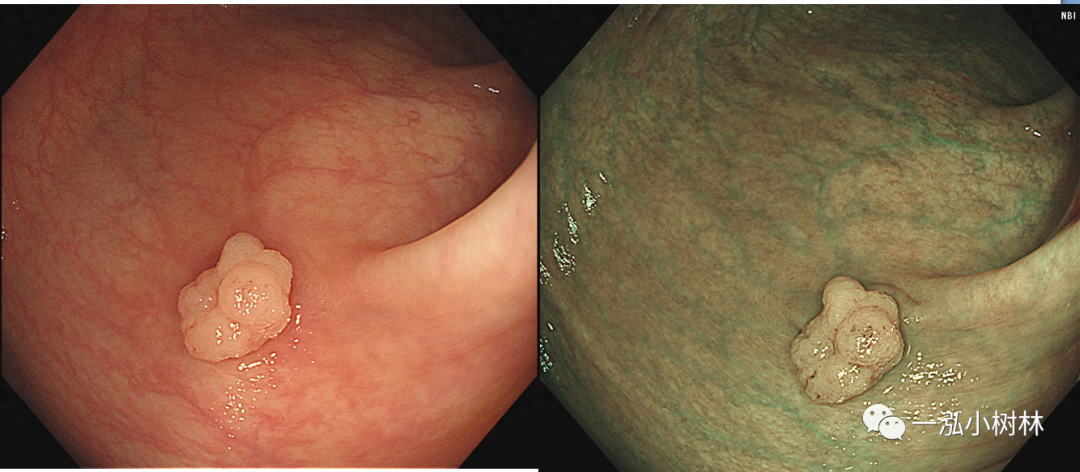

图2 结肠管状腺瘤(Pit Pattern IIIL型)